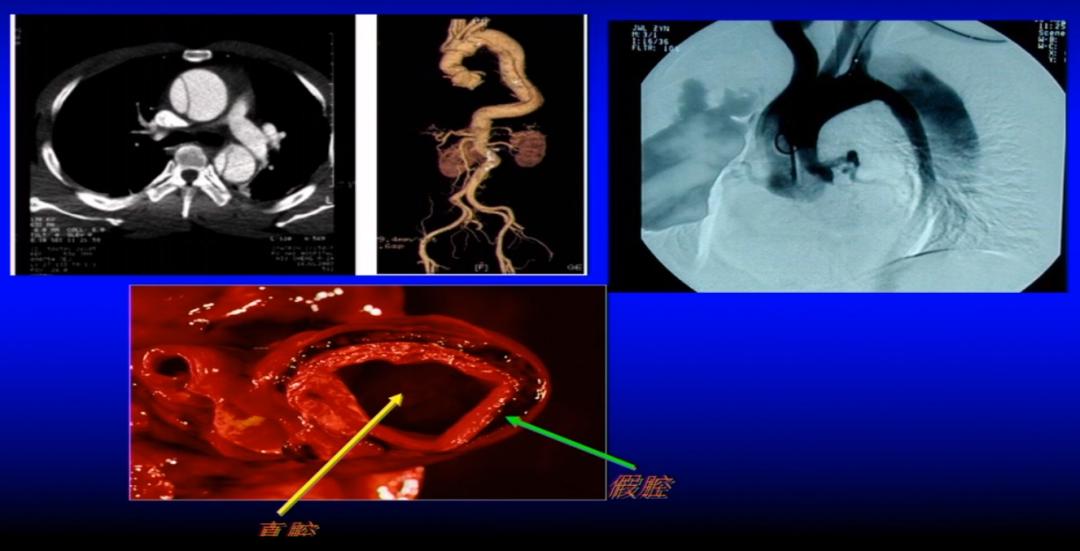

(1)定义: 主动脉夹层是指主动脉腔内的血液从主动脉内膜撕裂口进入主动脉中膜,并沿主动脉长轴方向扩展,造成主动脉真假两腔分离的一种病理改变,因通常呈继发瘤样改变,故将其称为主动脉夹层动脉瘤。

主动脉夹层的病理改变

主动脉夹层的影像学表现